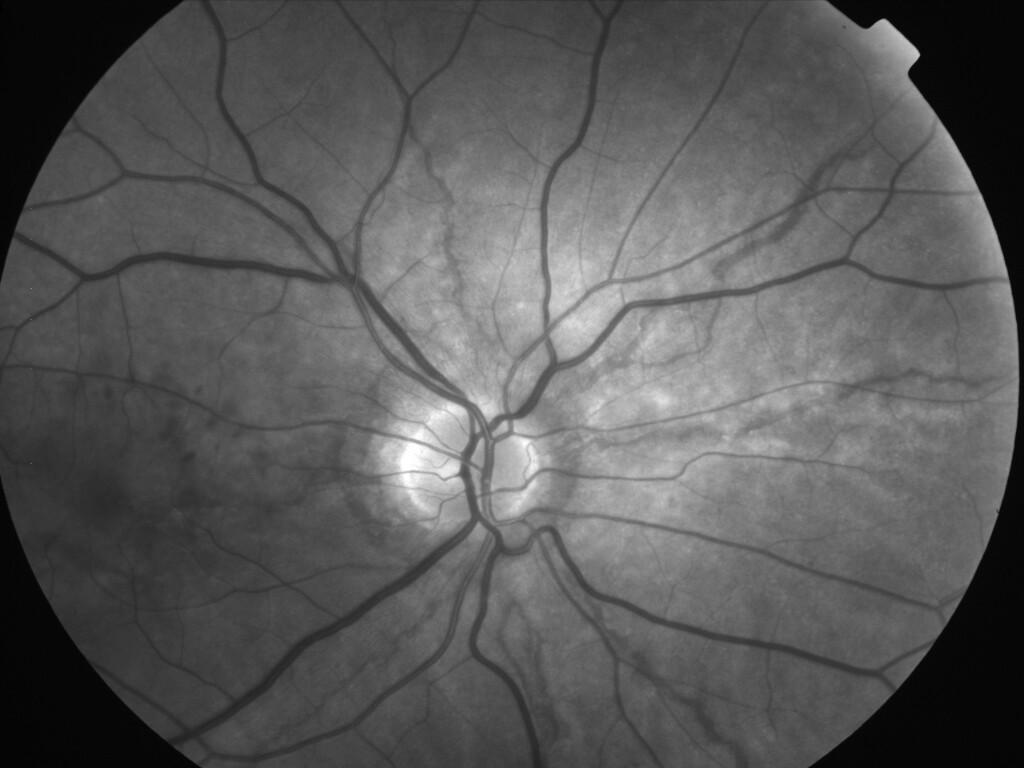

ASSOCIATION STRIES ANGIOIDES ET DYSROPHIE MACULAIRE RETICULEE

NEOVASCULARISATION